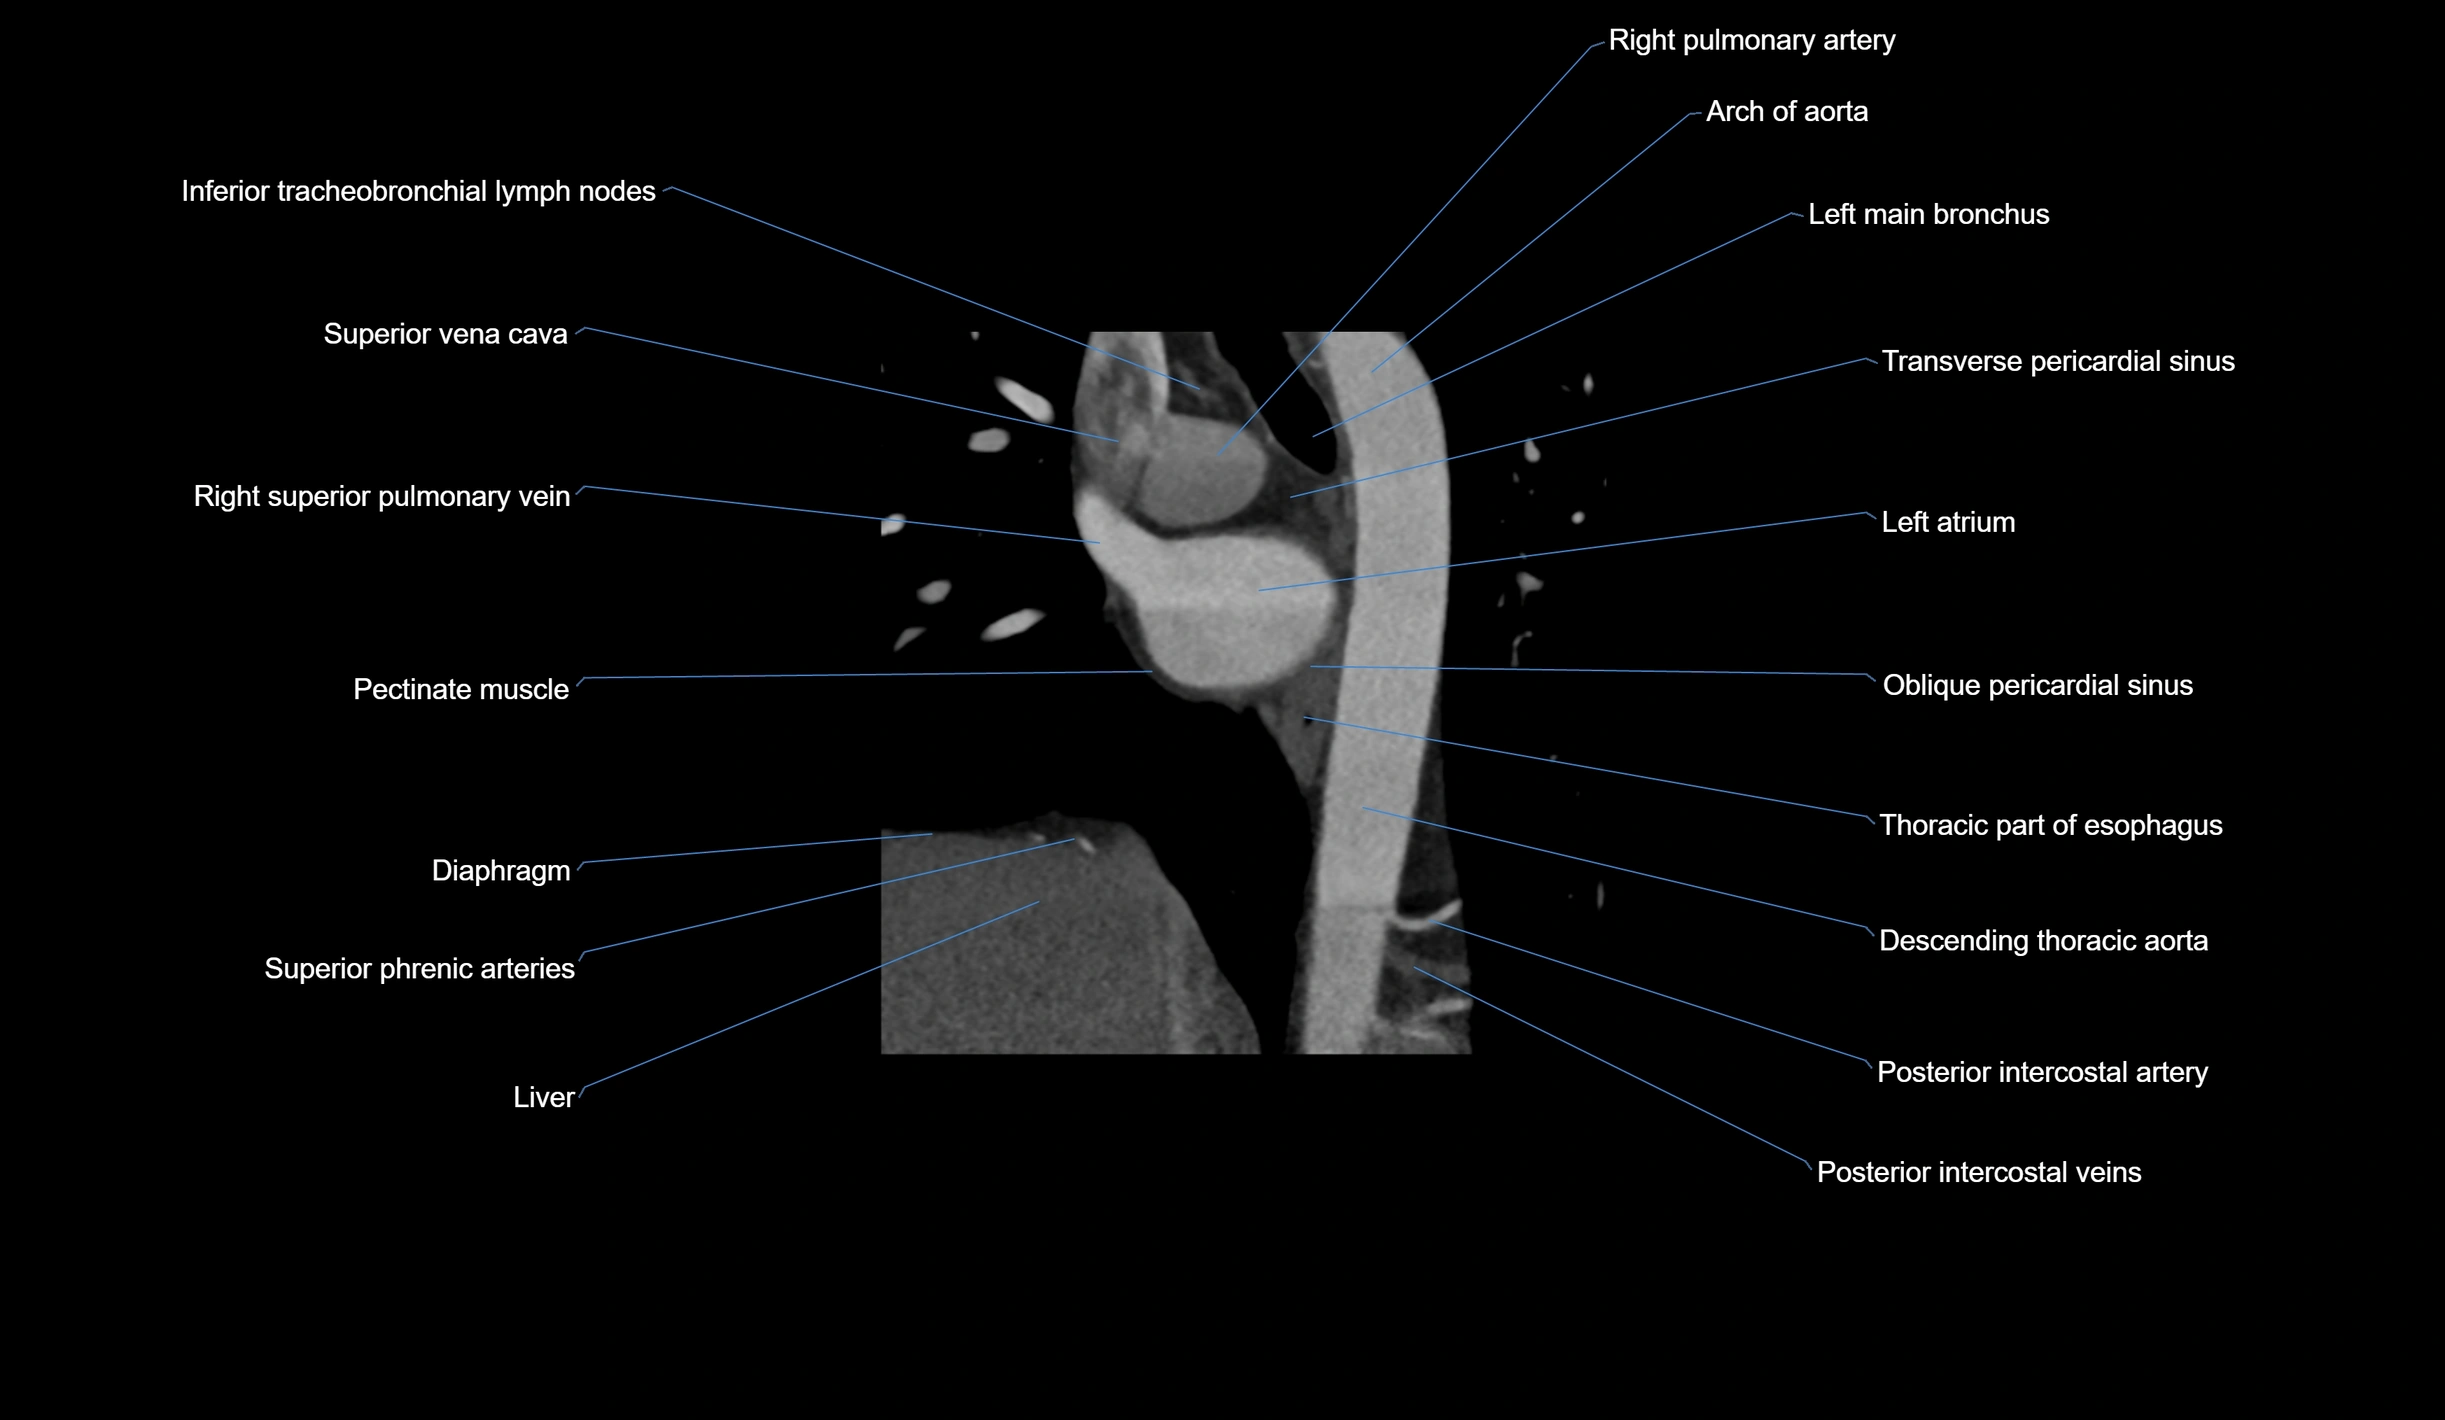

- Arch of aorta

- Descending thoracic aorta

- Inferior tracheobronchial lymph nodes

- Left atrium

- Left main bronchus

- Oblique pericardial sinus

- Pectinate muscles

- Posterior intercostal arteries

- Posterior intercostal veins

- Right pulmonary artery

- Right superior pulmonary vein

- Superior vena cava

- Transverse pericardial sinus